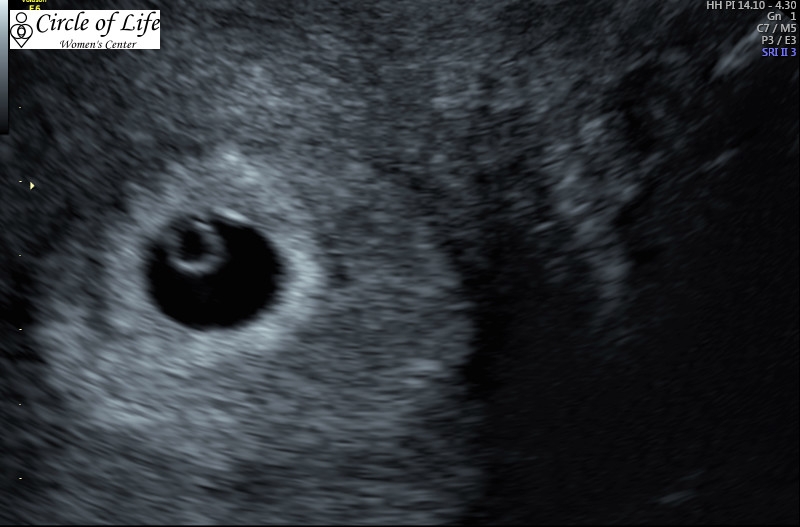

First ultrasound today! Yolk sac on the left. Heartbeat was strong at 155 bpm. I totally cried when I heard it-surprised myself. Also I miscalculated my due date so I'll be joining the ladies on tomorrow's ticker change!